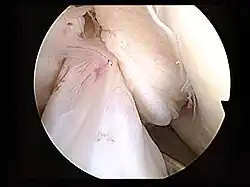

Die höchste diagnostische Sicherheit bietet die diagnostische Arthroskopie (Gelenkspiegelung). Dieses Verfahren stellt für die Diagnosestellung des Kreuzbandrisses den Goldstandard dar. Das Verfahren ist zwar minimalinvasiv, stellt aber in jedem Fall einen mit gewissen Risiken behafteten chirurgischen Eingriff in das Knie des Patienten dar.[94] Da jedoch die operative Behandlung eines Kreuzbandrisses in der Regel arthroskopisch (therapeutische Arthroskopie) durchgeführt wird, ergibt sich die Möglichkeit die Therapie, beispielsweise in Form einer Kreuzbandteilresektion (bei Anriss) oder einer Refixation des ausgerissenen Bandes, unmittelbar nach der diagnostischen Arthroskopie durchzuführen. Mit der zunehmenden Verbreitung von Kernspintomographen hat die Anzahl der rein diagnostischen Arthroskopien in den letzten Jahren deutlich abgenommen.[95][96] Die diagnostische Arthroskopie ist aber nach wie vor zur sicheren Abklärung der Diagnose einer Kreuzbandruptur – bei unklarer klinischer Befundung und unklarer MRT – das Mittel der Wahl.[94]

Arthroskopie

Der eigentliche Eingriff beginnt mit der Einführung des Arthroskops in das Knie des Patienten. Die Diagnose »Kreuzbandriss« kann so nochmals bestätigt werden. Andere Verletzungen, insbesondere des Meniskus, können vor der Rekonstruktion des Kreuzbandes versorgt werden.